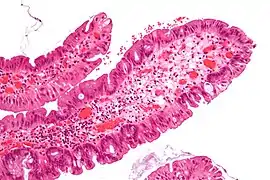

| Juvenile Polyp | Upper GI tract and colon | Cystically dilated glands with expanded lamina propria | Not inherently, may develop dysplasia | ![]() |

Juvenile polyposis syndrome, identical polyps in Cronkhite–Canada syndrome |